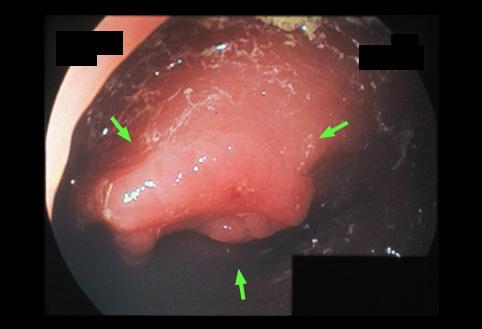

Criteria of Hist.ClassificationMalignant epithelial tumor/Adenocarcinoma

LocationLarge intestine(Colon)/Transverse colon

Technique, MethodEndoscopy

Macroscopic TypesType 0/IIc (IIc+IIa) Superficial depressed and elevated type

Size15 - 19

Depth of Tumor Invasionsubmucosa